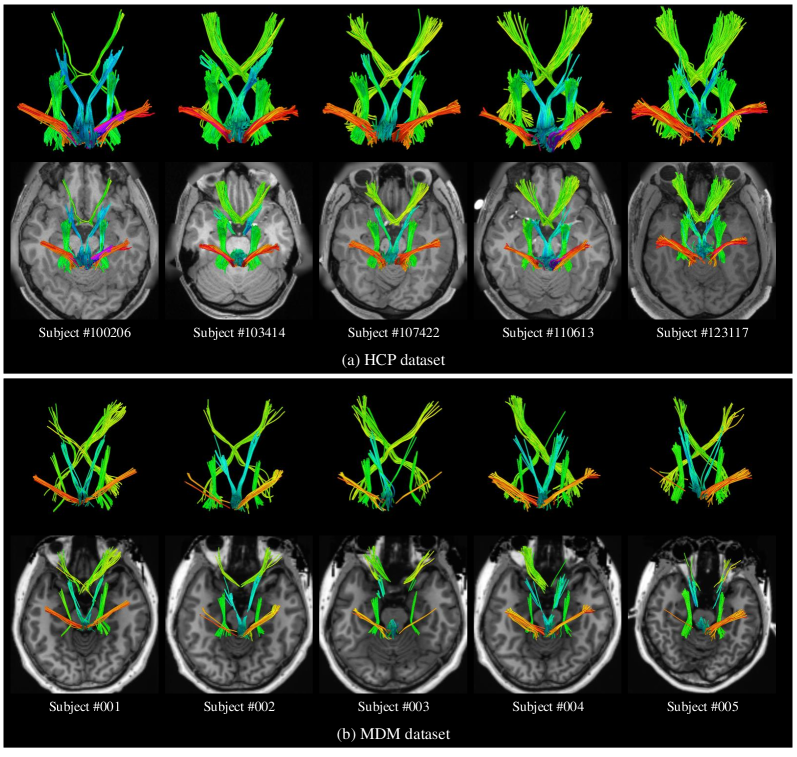

Refer to caption

Figure 3: Examples of the CN pathway reconstruction results using the proposed CN atlas on HCP dataset and MDM dataset. The tractogram is color-coded in average directional color using the ’Color Fibers By Mean Orientation’ buttons of the TractographyDisplay Module of the 3D Slicer.

To demonstrate the identification performance of the proposed CN atlas, we select different CN tracts from different subjects of the HCP dataset and the MDM dataset for qualitative comparison. Fig. 3(a) gives the CN pathway reconstruction results of subjects #100206, subjects #103414, subjects #107422, subjects #110613 and subjects #123117 using the proposed CN atlas on the HCP dataset, respectively. Fig. 3(b) shows the CN pathway reconstruction results of subjects #001, subjects #002, subjects #003, subjects #004 and subjects #005 using the proposed CN atlas on the MDM dataset, respectively. The top and bottom rows of Figs. 3(a) and  3(b) provide the 3D views of the identified CNs and displays of the 3D view superimposed on the slice, respectively. The CNs identified by the proposed CN atlas conform to the anatomical shape and fit the anatomical location on the slice.

The proposed CN atlas successfully reconstructed all 5 pairs of CNs (II, III, V, VII/VIII) in individual subjects and achieved a 100% identification rate for manually verifiable CNs across the cohort. Quantitative evaluation revealed strong spatial agreement between automated and manual selection methods [7, 21, 32, 37], with mean CN spatial overlap scores of 0.7448 (HCP subjects) and 0.7827 (MDM subjects)-exceeding the 0.72 threshold recommended by Cousineau et al. [34]. Visual assessment confirmed highly similar fiber trajectories with robust spatial correspondence (Fig. 3). Importantly, these overlap scores are comparable to or exceed those reported for state-of-the-art single-pair CN atlases applied to individual nerves, such as CN II [17], CN III [18], CN V [19], and CN VII/VIII [20]. This demonstrates that our multi-nerve approach achieves similar fidelity without sacrificing accuracy. We further demonstrated the method’s robustness and reliability for CN identification using a dataset of 20 MDM subjects and two PA patients.

We establish the anatomical validity of the proposed CN atlas in recognizing 5 pairs of CNs through multiple lines of evidence. First, the automatically identified CNs show high comparability to manual CN selection results, with visually similar fiber trajectories and strong spatial overlap (Fig. 3). Second, the anatomical validity of automatically recognized CNs was confirmed in patient data. As shown in Fig. 4, when a tumor compressed the optic nerve (CN II) along its pathway between the optic chiasm and lateral geniculate nucleus, our method successfully reconstructed the surrounding nerve fibers. This capability is critical for preoperative tumor resection planning. Finally, intraoperative validation in a CP patient confirmed that automatically identified nerves maintained clear spatial relationships with tumor locations.